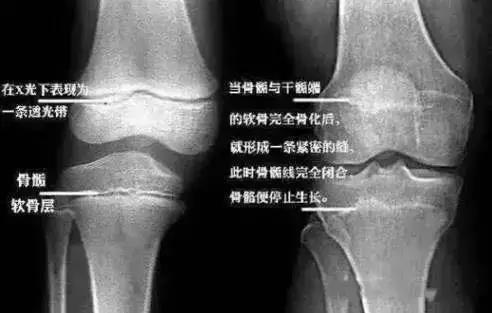

相反现在的小朋友由于营养的过剩,不少青少年甚至十三四岁骨骺线就已闭合,因此,家长切不可拿孩子的未来赌“晚长”的概率。

医生说倩倩的骨骺线已经快闭合,长个的空间已经很少了……

医学临床研究表明:一旦骨骺闭合,无论任何方法,都不可能再长高。